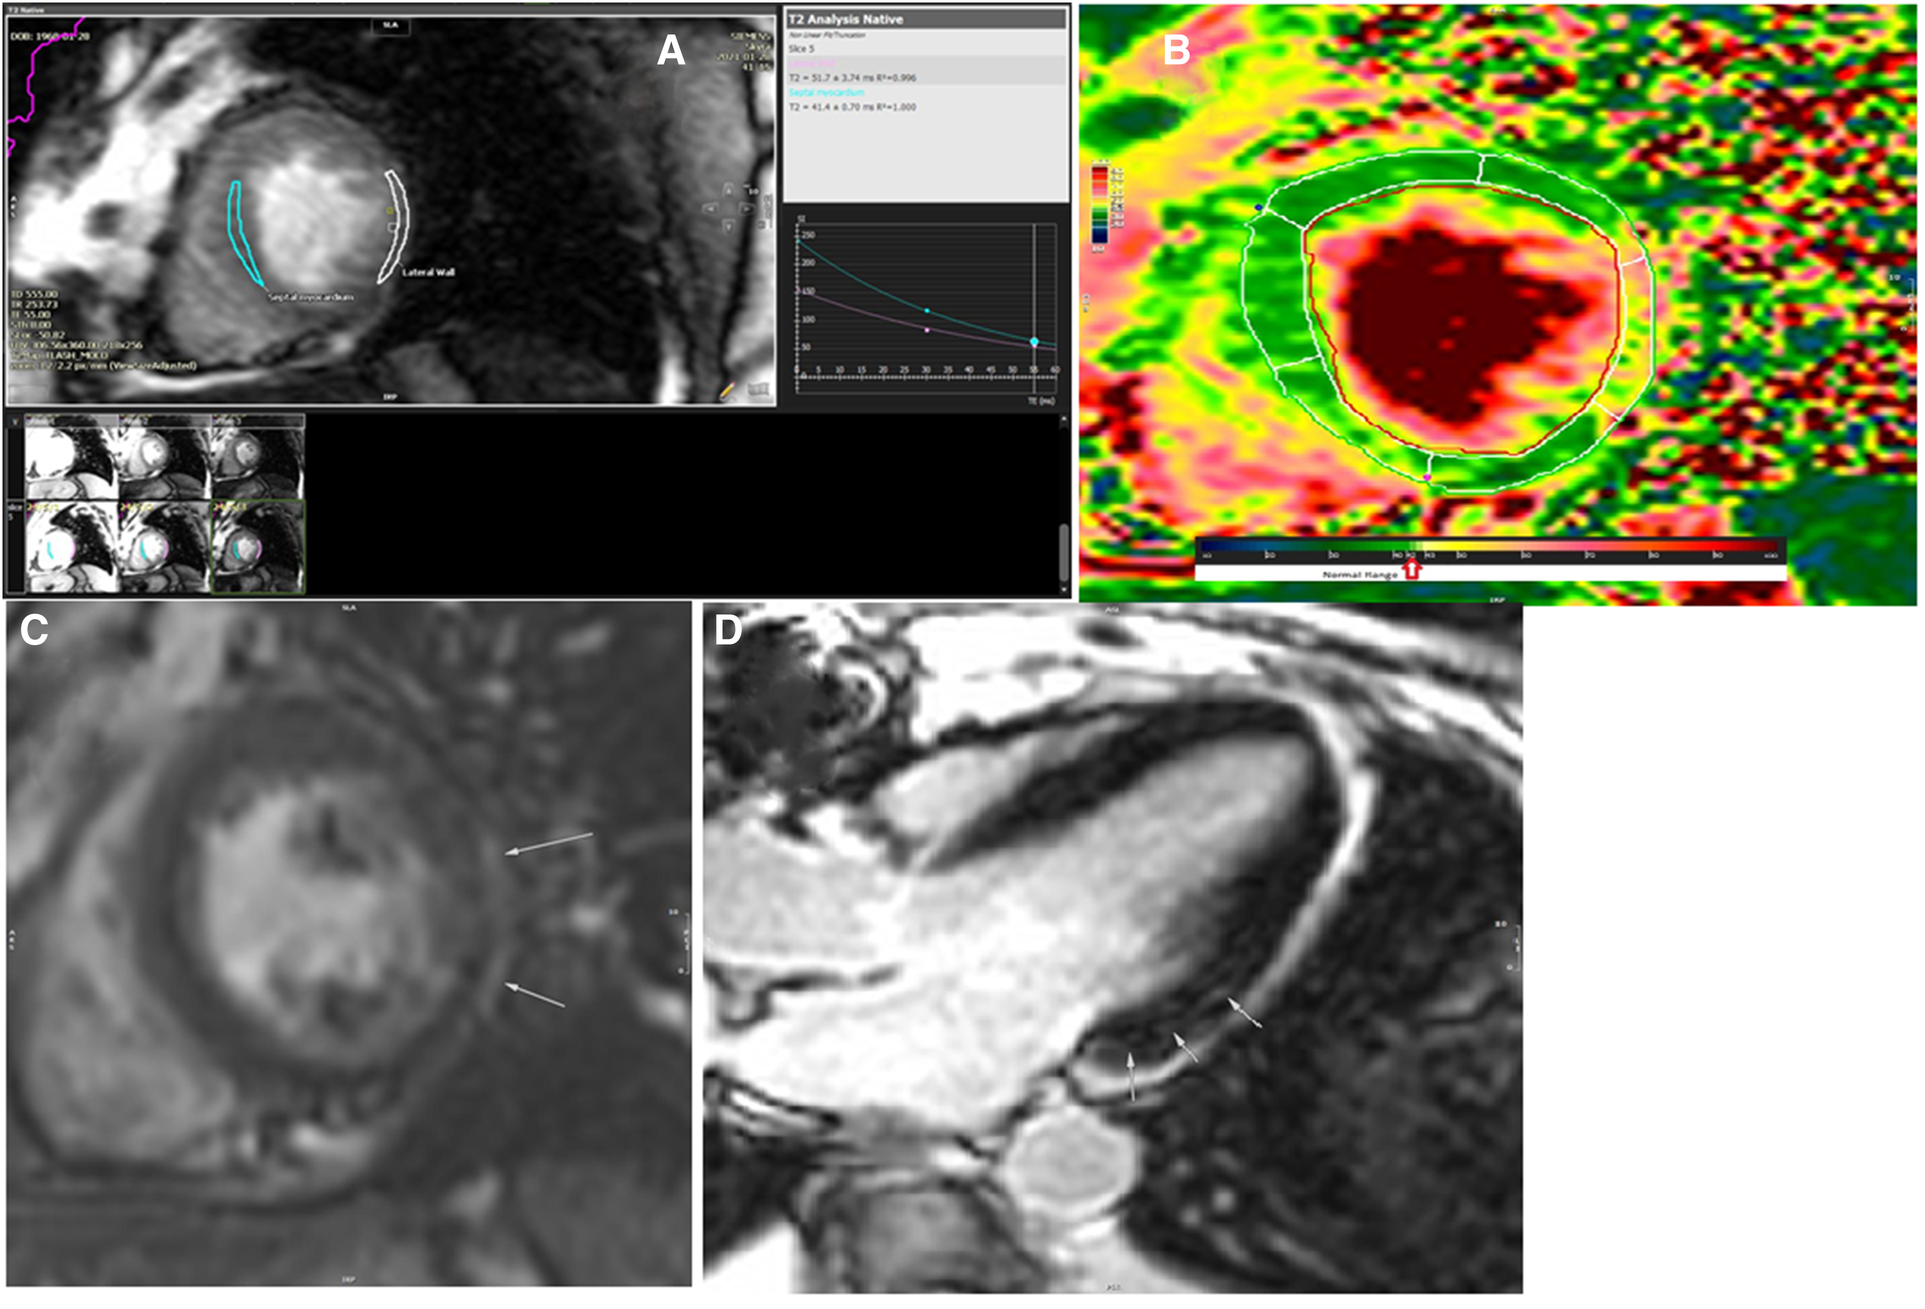

The patient did not accept to undergo endomyocardial biopsy. CMR was performed using a Siemens Skyra 3 T MRI scanner with the application of real-time cine images of LV, short inversion time inversion-recovery (STIR) T2-weighted image (T2WI), T2 mapping, native and postcontrast T1 mapping, and delayed postcontrast images. The results of CMR showed diffuse myocardial inflammation in T1 mapping and extracellular volume (ECV) map of LV, mid-wall late gadolinium enhancement (LGE) in basal segments of the interventricular septum (IVS), and subepicardial delayed enhancement in the basal inferolateral segments of LV without an ischemic pattern of myocardial injury (Figure 4). The regions marked as LGE on MRI refer to the presence of fibrosis in the patient. Matching the patient's clinical signs and symptoms with the European guideline for clinically suspected myocarditis, the diagnosis was considered as active myocarditis.

Figure 4

The results of cardiac magnetic resonance imaging after the radiation (A–D). (A) T2 analysis of mid-septal and mid-lateral segments of the left ventricle revealed prolongation of T2 relaxation time in the mid to apical segments of the lateral wall (52 ms). (B) T2 map image of the left ventricle in short axis view showed abnormal T2 value in the mid-lateral segment of the left ventricle. (C) Delayed postcontrast image of the left ventricle in short axis view showed a subepicardial rim of late gadolinium enhancement on the lateral wall of the left ventricle. (D) Delayed postcontrast image of the left ventricle in long axis three-chamber axis view revealed small focal subepicardial to mid-wall patches of late gadolinium enhancement in the basal inferolateral segment.